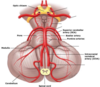

Vilka kärl försörjer hjärnstam och cerebellum?

- Från a. vertebralis –> PICA

- Från a. basilaris –> AICA

- Från a. basilaris –> aa. ad pontem